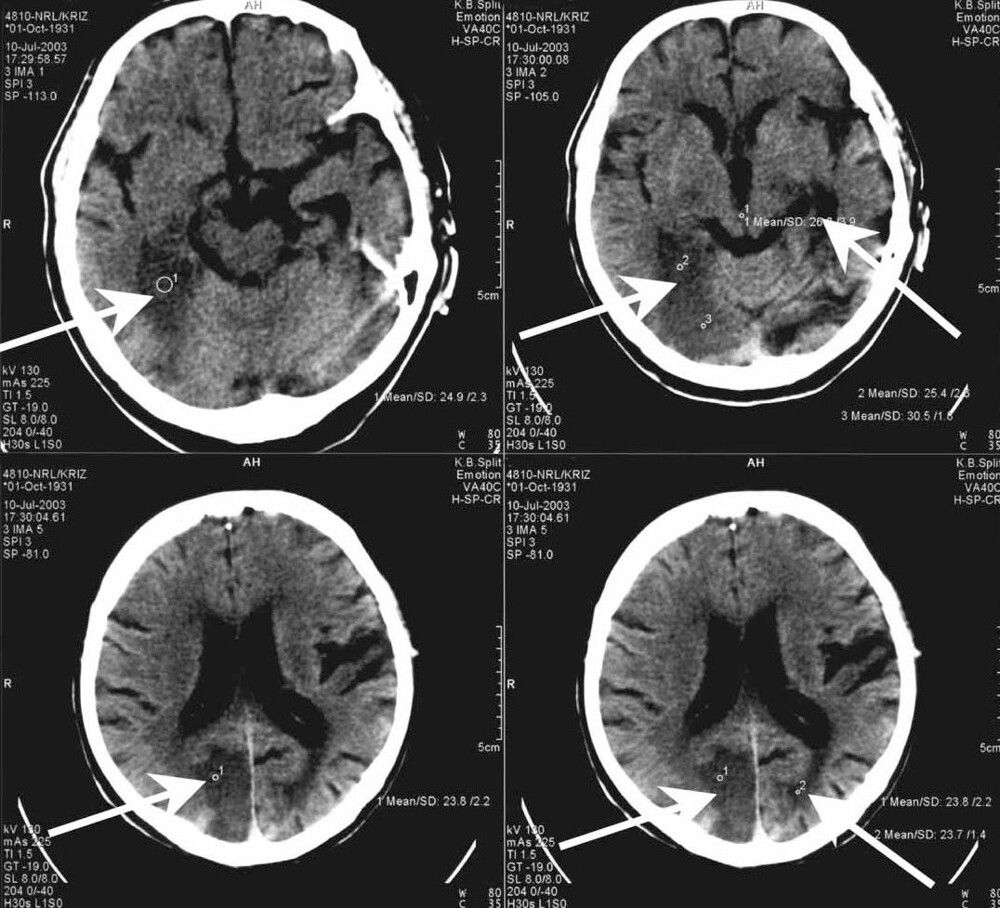

Синдром Антона-Бабинского (анозогнозия слепоты) - это редкий тип повреждения мозга, при котором человек полностью теряет зрение, но абсолютно не осознает свою слепоту. Слепота вызывается повреждением зрительной области головного мозга, которое обычно провоцирует инсульт или новообразование.